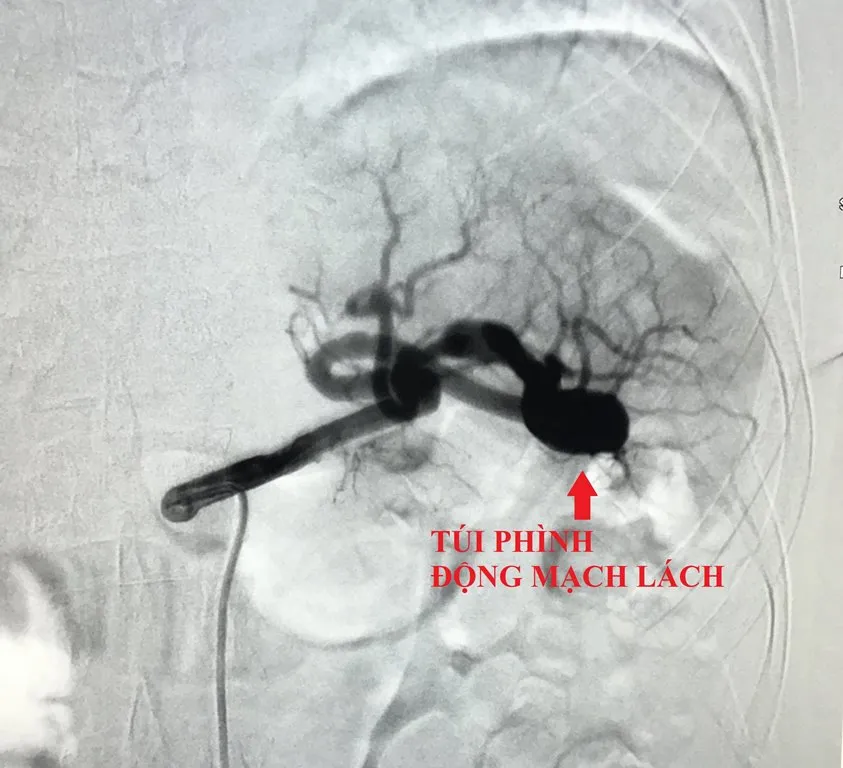

Vừa qua, các bác sĩ tại khoa Tim mạch 1, Bệnh viện (BV) Nguyễn Trãi (Quận 5, TP.HCM) cho biết vừa can thiệp thành công một trường hợp bị phình động mạch lách nguy hiểm. Bệnh nhân NTTT (44 tuổi, ngụ quận 3, TP.HCM) đến thăm khám đau bụng âm ỉ, khó chịu.

Sau khi được siêu âm bụng và mạch máu, chụp CT scan, các bác sĩ phát hiện chị có túi phình ở động mạch lách, nguy cơ vỡ đe dọa tính mạng. Bệnh nhân được yêu cầu nhập viện ngay để điều trị.

Túi phình động mạch lách của người bệnh. Ảnh: BVCC